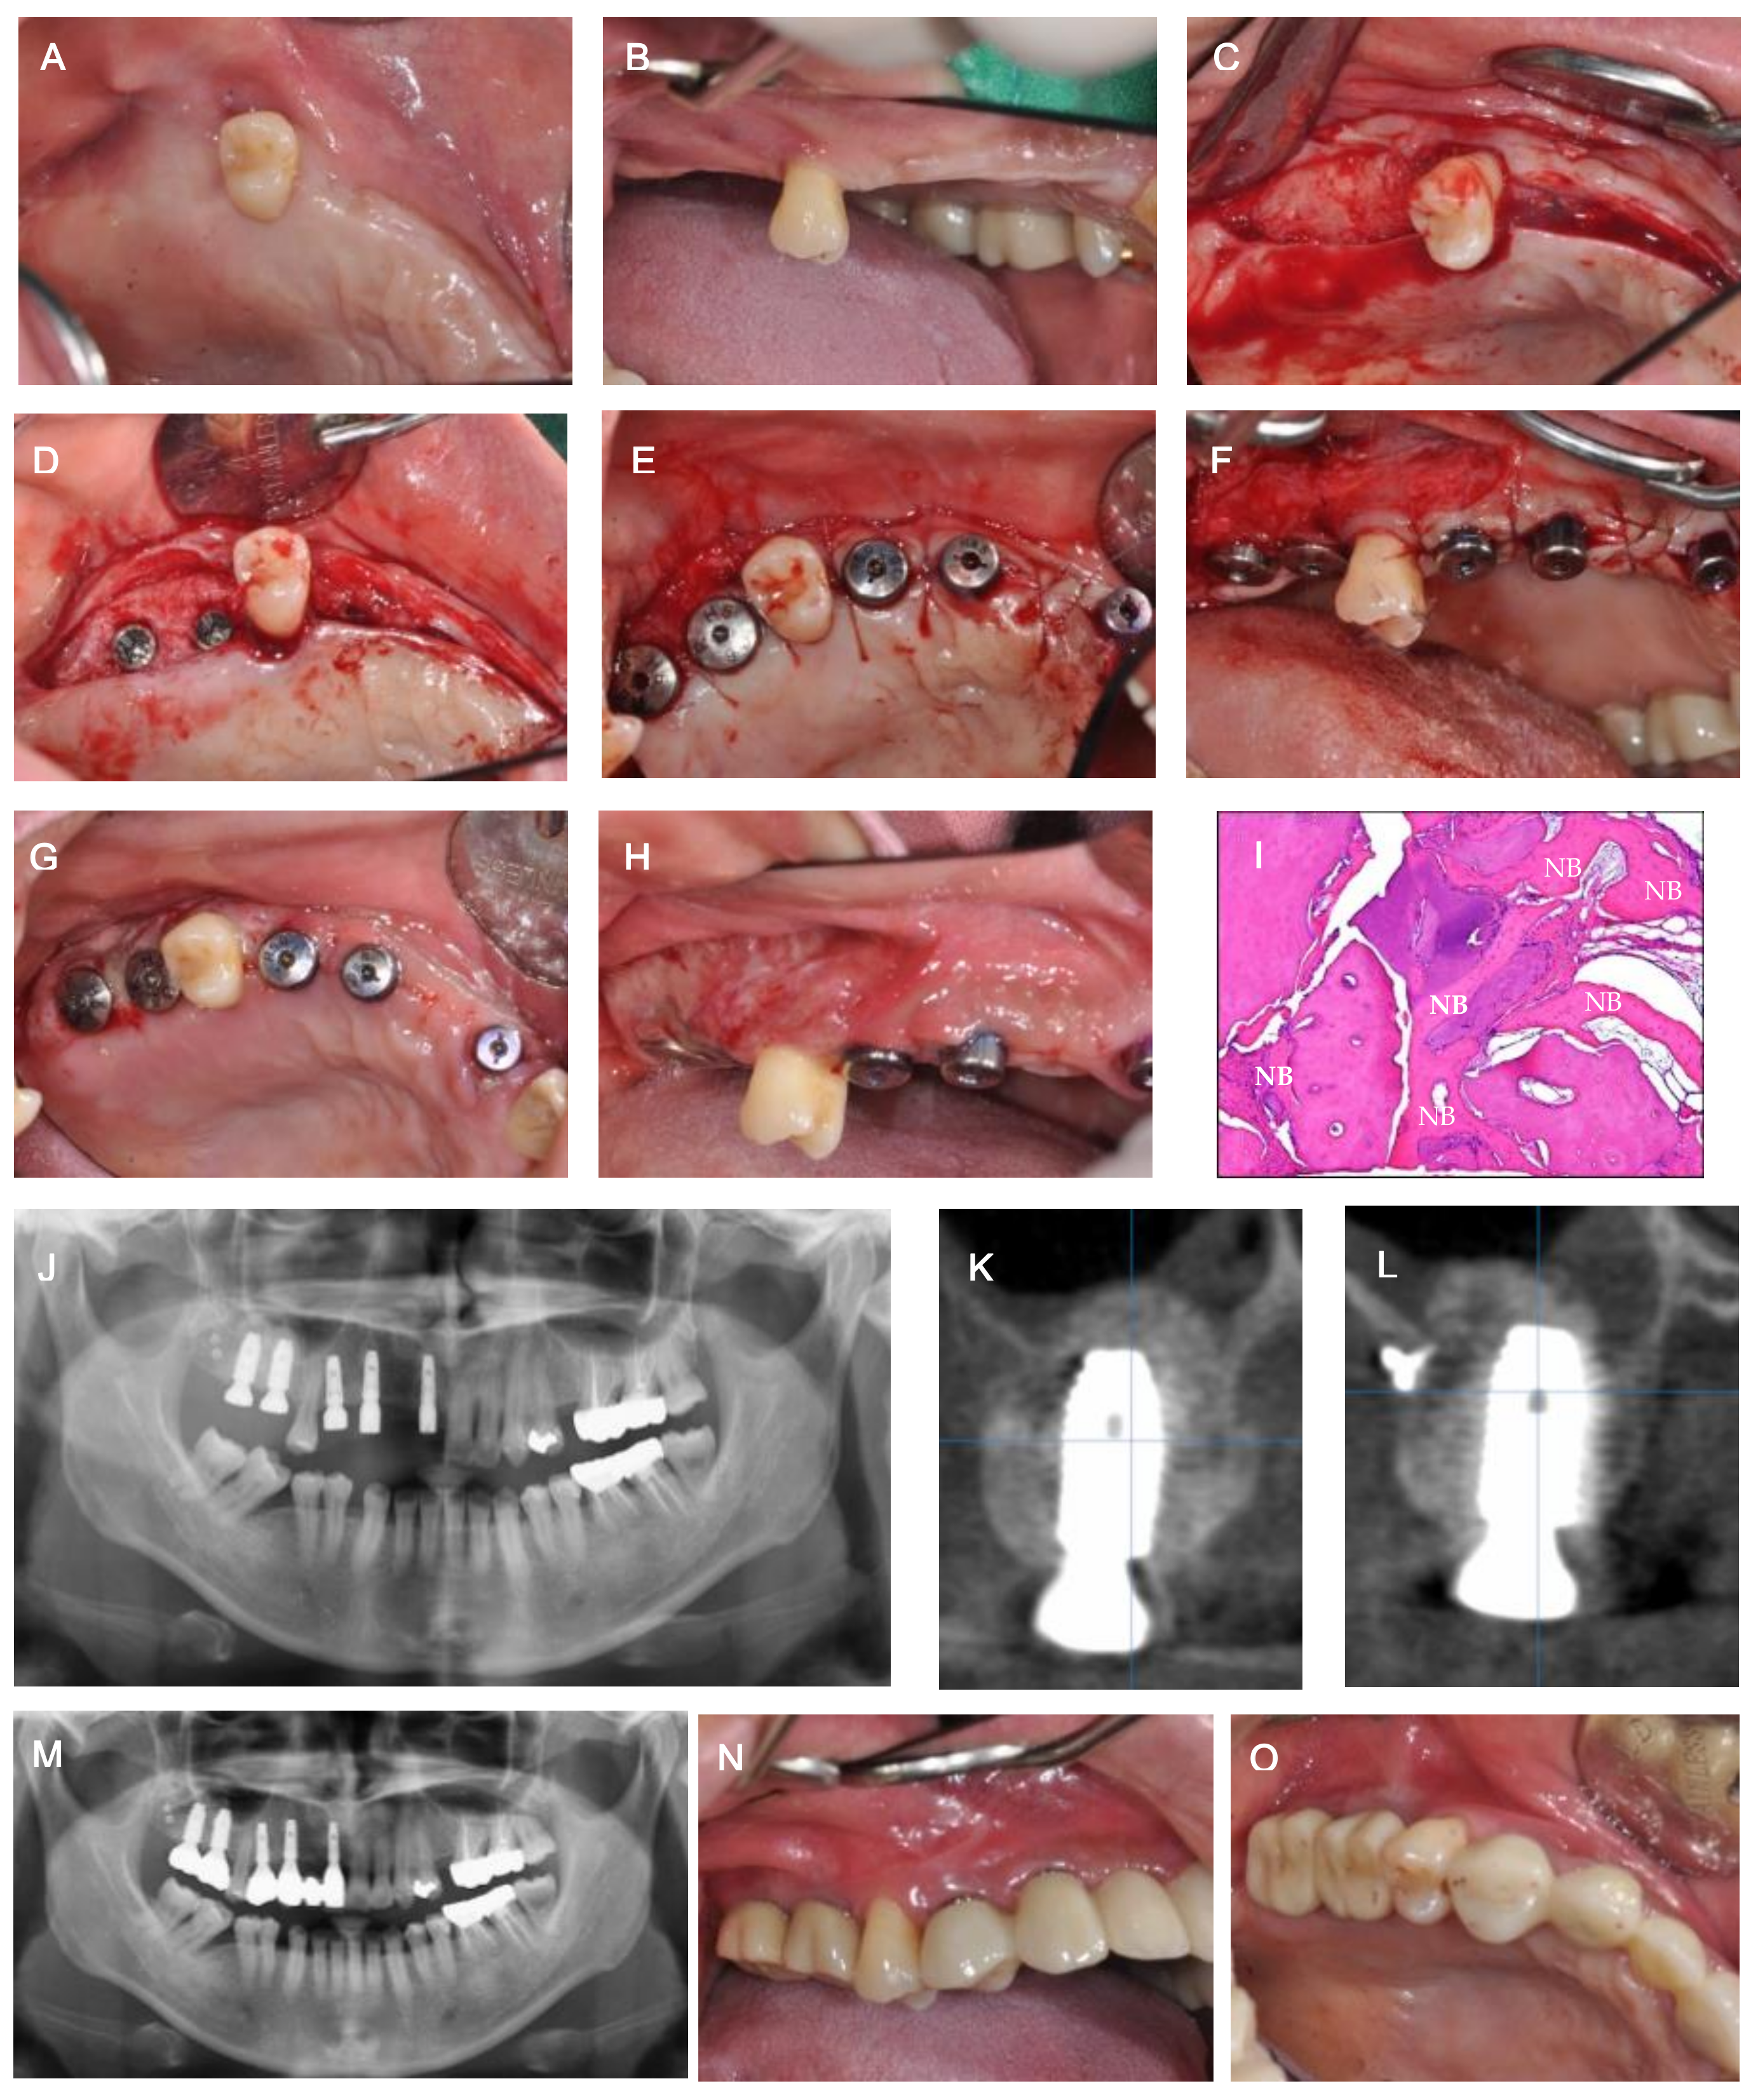

Implant Placement after Closure of Oroantral Communication by Sinus Bone Graft Using a Collagen Barrier Membrane in the Shape of a Pouch: A Case Report and Review of the Literature

2. Case Description